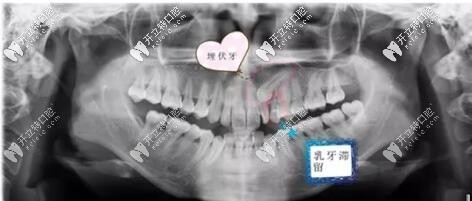

正畸配合阻生齒牽引技術(shù),使得小羅半埋伏的虎牙成功就位

阻生牙埋伏牙牙齒牽引術(shù)虎牙發(fā)布時間: 2024-12-05

正畸本就是個復雜的學科,如果在正畸途中再遇到阻生齒或埋伏齒,更是增加難度。不過,只要通過合理的阻生牙牽引術(shù)+正畸,也能達到牙列牙弓排齊,阻生齒復位的理想效果。